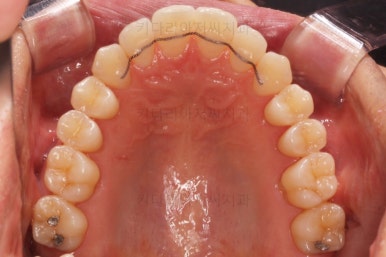

어느 정도 진행이 되었다 싶으면 윗니도 장치를 부착해서 가지런하게 해줘요.

윗니도 장치를 부착했어요.

아랫니보다 해야 할 작업이 많지 않기 때문에 이렇게 시간차를 두어 진행을 했고, 이렇게 하면 교정장치가 눈에 띄는 기간이 줄어들어 환자분의 만족도는 더 올라가게 되죠.

아랫니 이 뽑은 자리는 거의 다 다물렸어요.

거꾸로 물리는 앞니도 어느 정도 많이 개선이 되었고요.

외모도 좋아졌고 교합도 개선되어 가고 있기 때문에 좀 더 정교한 마무리를 하고 치료 종료하기로 했어요. 모자렀던 부분도 더 가지런하게 하고 있어요.

점점 마무리에 가까워지고 있습니다.

좀 더 마무리를 하고 치료 종료하기로 했어요.